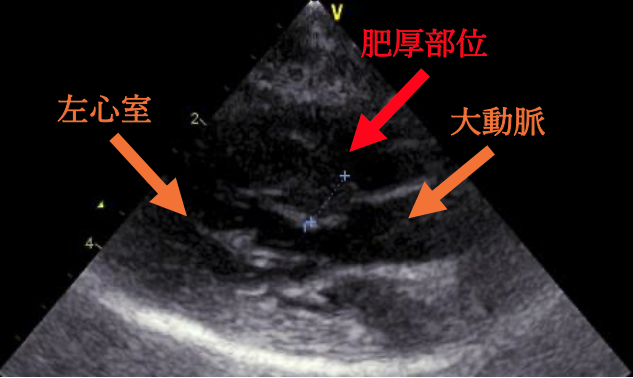

肥⼤型⼼筋症とは、左⼼室の壁が厚くなってしまい、⾎液をうまく送り出せなくなる病気です。その中でも「閉塞性肥⼤型⼼筋症」とは、左室流出路(左⼼室の出⼝)が、厚くなった⼼筋や僧帽弁によって狭くなるタイプを指します。

今回の⼼臓超⾳波検査では、 ⼤動脈へ流れる⾎液の速度がやや速くなっている所⾒が確認されました。現在、ねこちゃんに症状はありませんが、圧⼒が強い状態が続くと、⼼臓の筋⾁が厚くなったり不整脈を引き起こす可能性があるため、 お薬の量を調整しています。